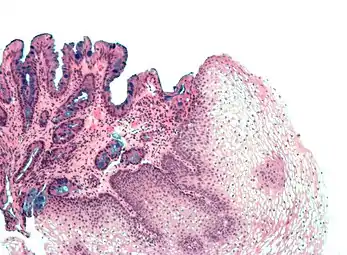

[Micrograph] of normal stratified squamous epithelium and the metaplasic epithelium of Barrett's esophagus (left of image). Alcian blue stain.

Non-keratinized stratified squamous epithelium, image highlights the epithelial nucleuses, rest of the epithelial layer, underlying connective tissue and other epithelia